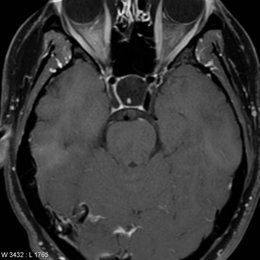

PREGUNTA 2 de 10

¿Cuál es el diagnóstico más probable de la siguiente imagen?

A)

quiste aracnoideo

B)

Quiste de la bolsa de Rathke

C)

craneofaringioma

D)

Silla turca vacía

E)

macroadenoma hipofisario